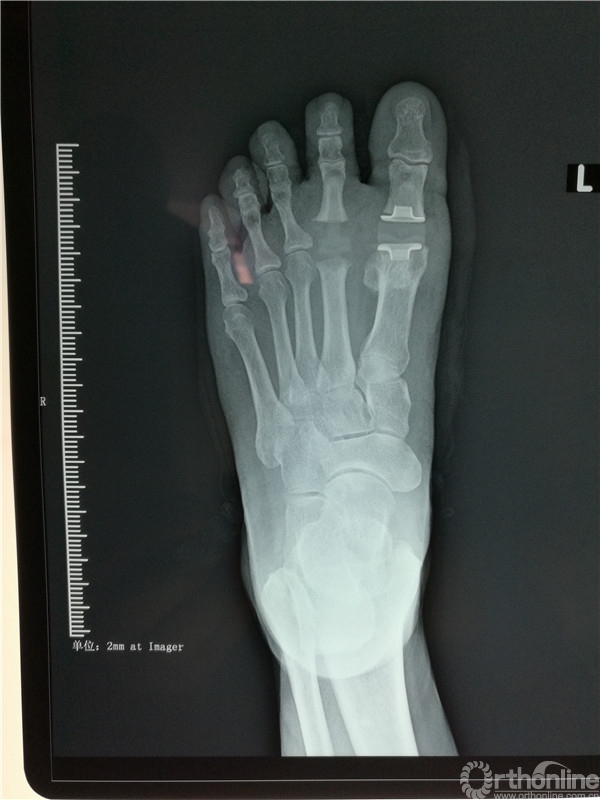

在张树栋院长及刘克贵主任的支持下,南院骨科组织多次病例讨论,制定了一套对病人有效的治疗方案。以刘克贵主任,孙冰,李宏彦组成的医疗小组。于2016年4月9日上午九时,在腰麻下行左足第1、2 跖趾关节人工关节置换术,患者术后左足的疼痛明显减轻,功能良好,外形美观。

烟台市烟台山医院南院骨科成功完成了胶东地区首例跖趾关节人工置换术。